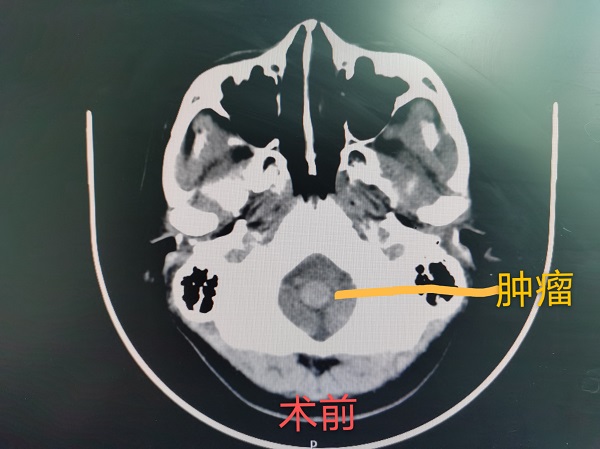

神經(jing)外科(ke)成(cheng)功完成(cheng)總醫(yī)院第30例腦幹腫瘤切除術(shù)

近日(ri),神經(jing)外科(ke)成(cheng)功完成(cheng)我(wo)院第30例腦幹腫瘤切除術(shù)。該患者爲(wei)一(yi)名(míng)37歲的(de)女性,因左側肢體(ti)活動(dòng)障礙入院治療,術(shù)中(zhong)見腫瘤位于(yu)延髓內(nei)部(bu),伴有(yǒu)出血,龐克軍主(zhu)任在(zai)顯微鏡下清(qing)除血腫,同時分(fēn)塊切除腫瘤,手術(shù)順利,術(shù)後(hou)患者肢體(ti)活動(dòng)恢複良好,按期出院。